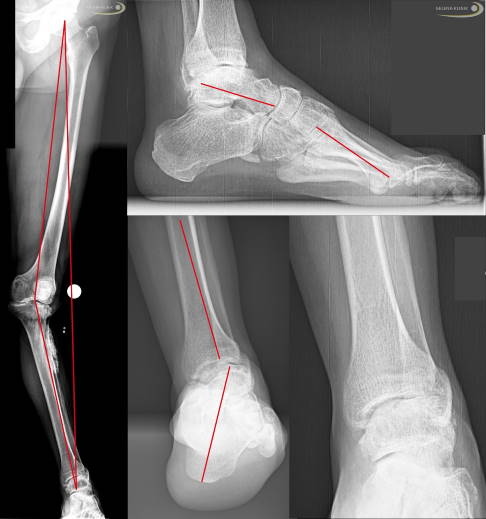

Fehlstellung des Fersenbeins

Im Rahmen der Charcot-Marie-Tooth-Erkrankung tritt auch eine Standunsicherheit auf. Diese ist abhängig von der Fehlstellung der Ferse. Die Ferse steht durch die normale Funktion der Wade und der innen liegenden Beugesehnen und hinteren Schienbeinsehne bei einer Schwächung der äußeren und vorne liegenden Sehnen nach innen gekippt (Varusstellung). Diese Verkippung führt vermehrt zum Umknicken des Fußes. Die Standbasis-Fläche wird durch die Belastung auf dem Außenrand geringer. Dies reduziert die Beweglichkeit im oberen Sprunggelenk. Ursächlich sind die veränderten Zugverhältnisse, aber auch ein knöcherner Anschlag (Impingement) am vorderen Sprunggelenk durch die veränderte Fußform. Die Veränderungen sind durch die Schädigung der motorischen Nerven erklärbar.

Fehlstellungen des Rückfußes

Die Charcot-Marie-Tooth-Erkrankung wirkt sich nicht nur auf den Fuß und auf die Zehen aus, sondern auch auf den Rückfuß. Die Auswirkungen auf den Rückfuß durch die veränderten Muskelzüge können teilweise gut kompensiert werden. Zum Teil entstehen durch die resultierende Fehlstellung – häufig in Kombination mit Verletzungen der Bänder – weitreichende Schädigungen des Sprunggelenkes. Die Fehlstellung wirkt sich dann auch auf das gesamte Bein aus. So können X-Beinachsen entstehen. Durch die Fehlstellung des Fußes resultiert häufig auch eine veränderte Rotation im Unterschenkel. Diese Auswirkungen können individuell sehr verschieden sein. Sie hängen sehr stark vom individuellen Befallsmuster ab. Die Prinzipien sind bei allen Patienten mit CMT-Erkrankungen ähnlich, aber nie gleich.